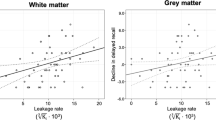

To assess whether health and lifestyle factors are related to BBB permeability in the hippocampus, thalamus or WM, we ran three separate multiple regression models with the hippocampus, thalamus or WM Ki as the dependent variable and all health parameters as regressors. An increased Ki in the WM was significantly associated with a diabetes diagnosis (p = 0.0149) and a higher BMI (p = 0.0079). Likewise, an increased Ki value in the thalamus was significantly associated with a diabetes diagnosis (p = 0.0161) and a higher Fazekas score in the periventricular white matter (PVWM) (p = 0.0237) (Fig. 4). Since multiple regression only includes pairwise complete observations, the full model only had 36 observations. Therefore, we ran a submodel with only the significant regressors as independent variables, which would include a larger sample size (n = 74). Diabetes was significant when run in the submodel as a single regressor for WM (p = 0.0398), and the thalamus was borderline significant (p = 0.0883). PVWM and BMI were no longer significant as a single regressor for any ROI, but the BMI showed a tendency towards significance (p = 0.0807) (Fig. 4).

Post hoc analysis of association between overall vascular risk factor and BBB permeability

To further examine the effect of vascular risk factors, we combined the risk factors into an overall vascular risk factor score. In this combined score, we included diabetes (yes/no), BMI and Fazekas score. Participants were assigned 0–3 points, depending on whether they had the vascular risk factors and to what extent. Points were assigned in the following manner: diabetes, if yes = 1 point, if no = 0 point. BMI, if equal to or more than 27 = 1, if less than 27 = 0 point. Fazekas scores were first averaged across DWM and PVWM, then divided by 3 to achieve a score ranging from 0 to 1. There was a significant association between vascular risk factors (N = 72) and Ki in the hippocampus (p = 0.015), thalamus (p = 0.007) and white matter (p = 0.001), where higher vascular risk factor was associated with increased Ki (Supplementary Fig. 1).